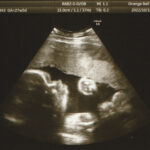

当院では患者さんから

エコーの写真をみせていただいても

その日の状態と違う場合もあるので

触診で赤ちゃんの位置と動き

お腹の張り等状態を確認します